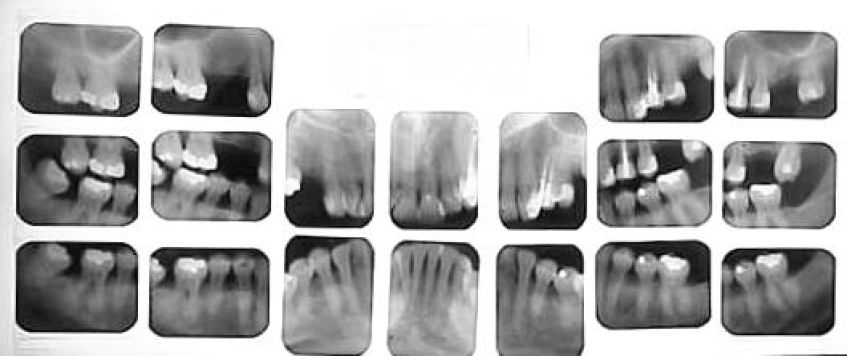

Когда необходим дентальный рентген?

Дентальный рентгенаппарат (радиовизиограф) используется в том случае, когда необходимо сделать прицельный снимок одного или нескольких зубов. Большое контрастное изображение на экране компьютера, а также возможность трёхмерной визуализации полученных снимков способствуют постановке точного, безошибочного диагноза стоматологом.

Дентальные снимки необходимы при лечении корневых каналов зубов, диагностике кариеса между зубами и под деснами, а также вторичного кариеса под пломбами и коронками.